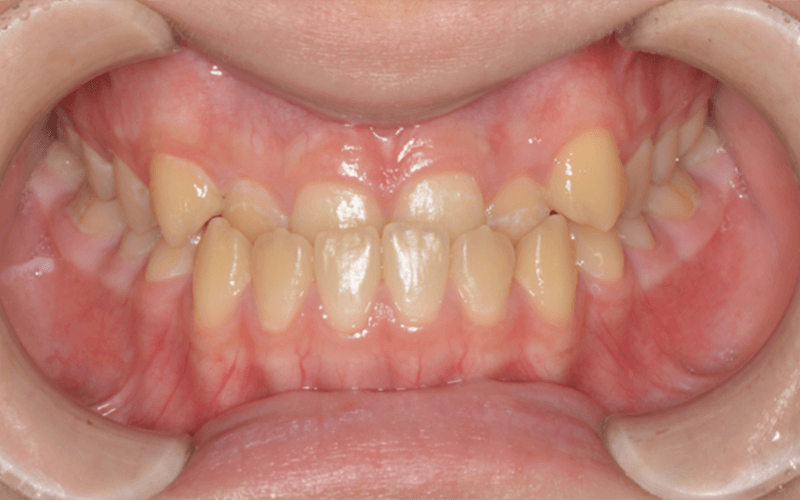

case.1 前歯のガタガタが

気になる

before

| 主訴 | 前歯のガタガタが 気になる |

|---|---|

| 治療期間 | 28ケ月 |

| 治療回数 | 30回 |

| 治療費 | 75万+税 |

| 治療内容 | クワドヘリックス バイヘリックス 上顎両側4番 7番抜歯 表側全体矯正 |

| リスク | 歯根吸収、歯肉退縮、 知覚過敏、歯の切削 |